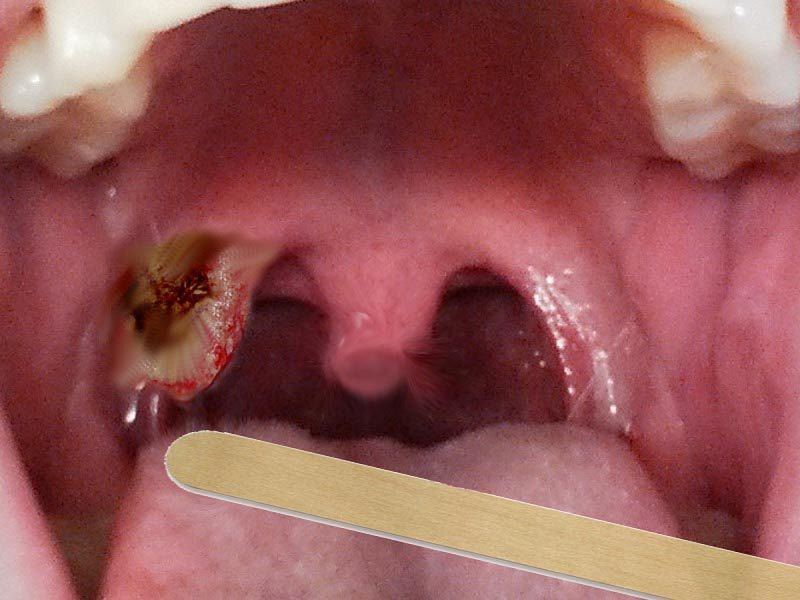

Bệnh nhân ung thư khoang miệng cần phải có chế độ ăn uống lành mạnh, khoa học để tăng cường sức đề kháng, đối phó lại căn bệnh ung thư. Dưới đây Nutri Fucoidan sẽ chia sẻ tới bạn đọc chế độ dinh dưỡng cho bệnh nhân ung thư khoang miệng khoa học và hợp lý nhất.

Ung thư khoang miệng và các phương pháp điều trị có thể gây ảnh hưởng tới vấn đề ăn uống của bệnh nhân, gây nên tình trạng khó nuốt khô miệng, thay đổi vị giác và sút cân. Việc ăn uống, nuốt thường gặp khó khăn hoặc đau đớn trong một thời gian dài khiến vấn đề dinh dưỡng của bệnh nhân bị ảnh hưởng. Vì vậy, trong quá trình điều trị ung thư, đa số người bệnh cần thay đổi chế độ dinh dưỡng cho bệnh nhân ung thư khoang miệng.

Đối với bệnh nhân ung thư khoang miệng, việc ăn uống trở nên khó khăn, dẫn đến nguy cơ suy kiệt cao. Vì thế, người bệnh cần kiên trì tuân thủ các hướng dẫn về chế độ dinh dưỡng từ bác sĩ và điều dưỡng để hỗ trợ quá trình phục hồi nhanh chóng.